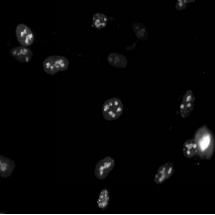

3、遗传学:用于基因表达研究和蛋白质定位。